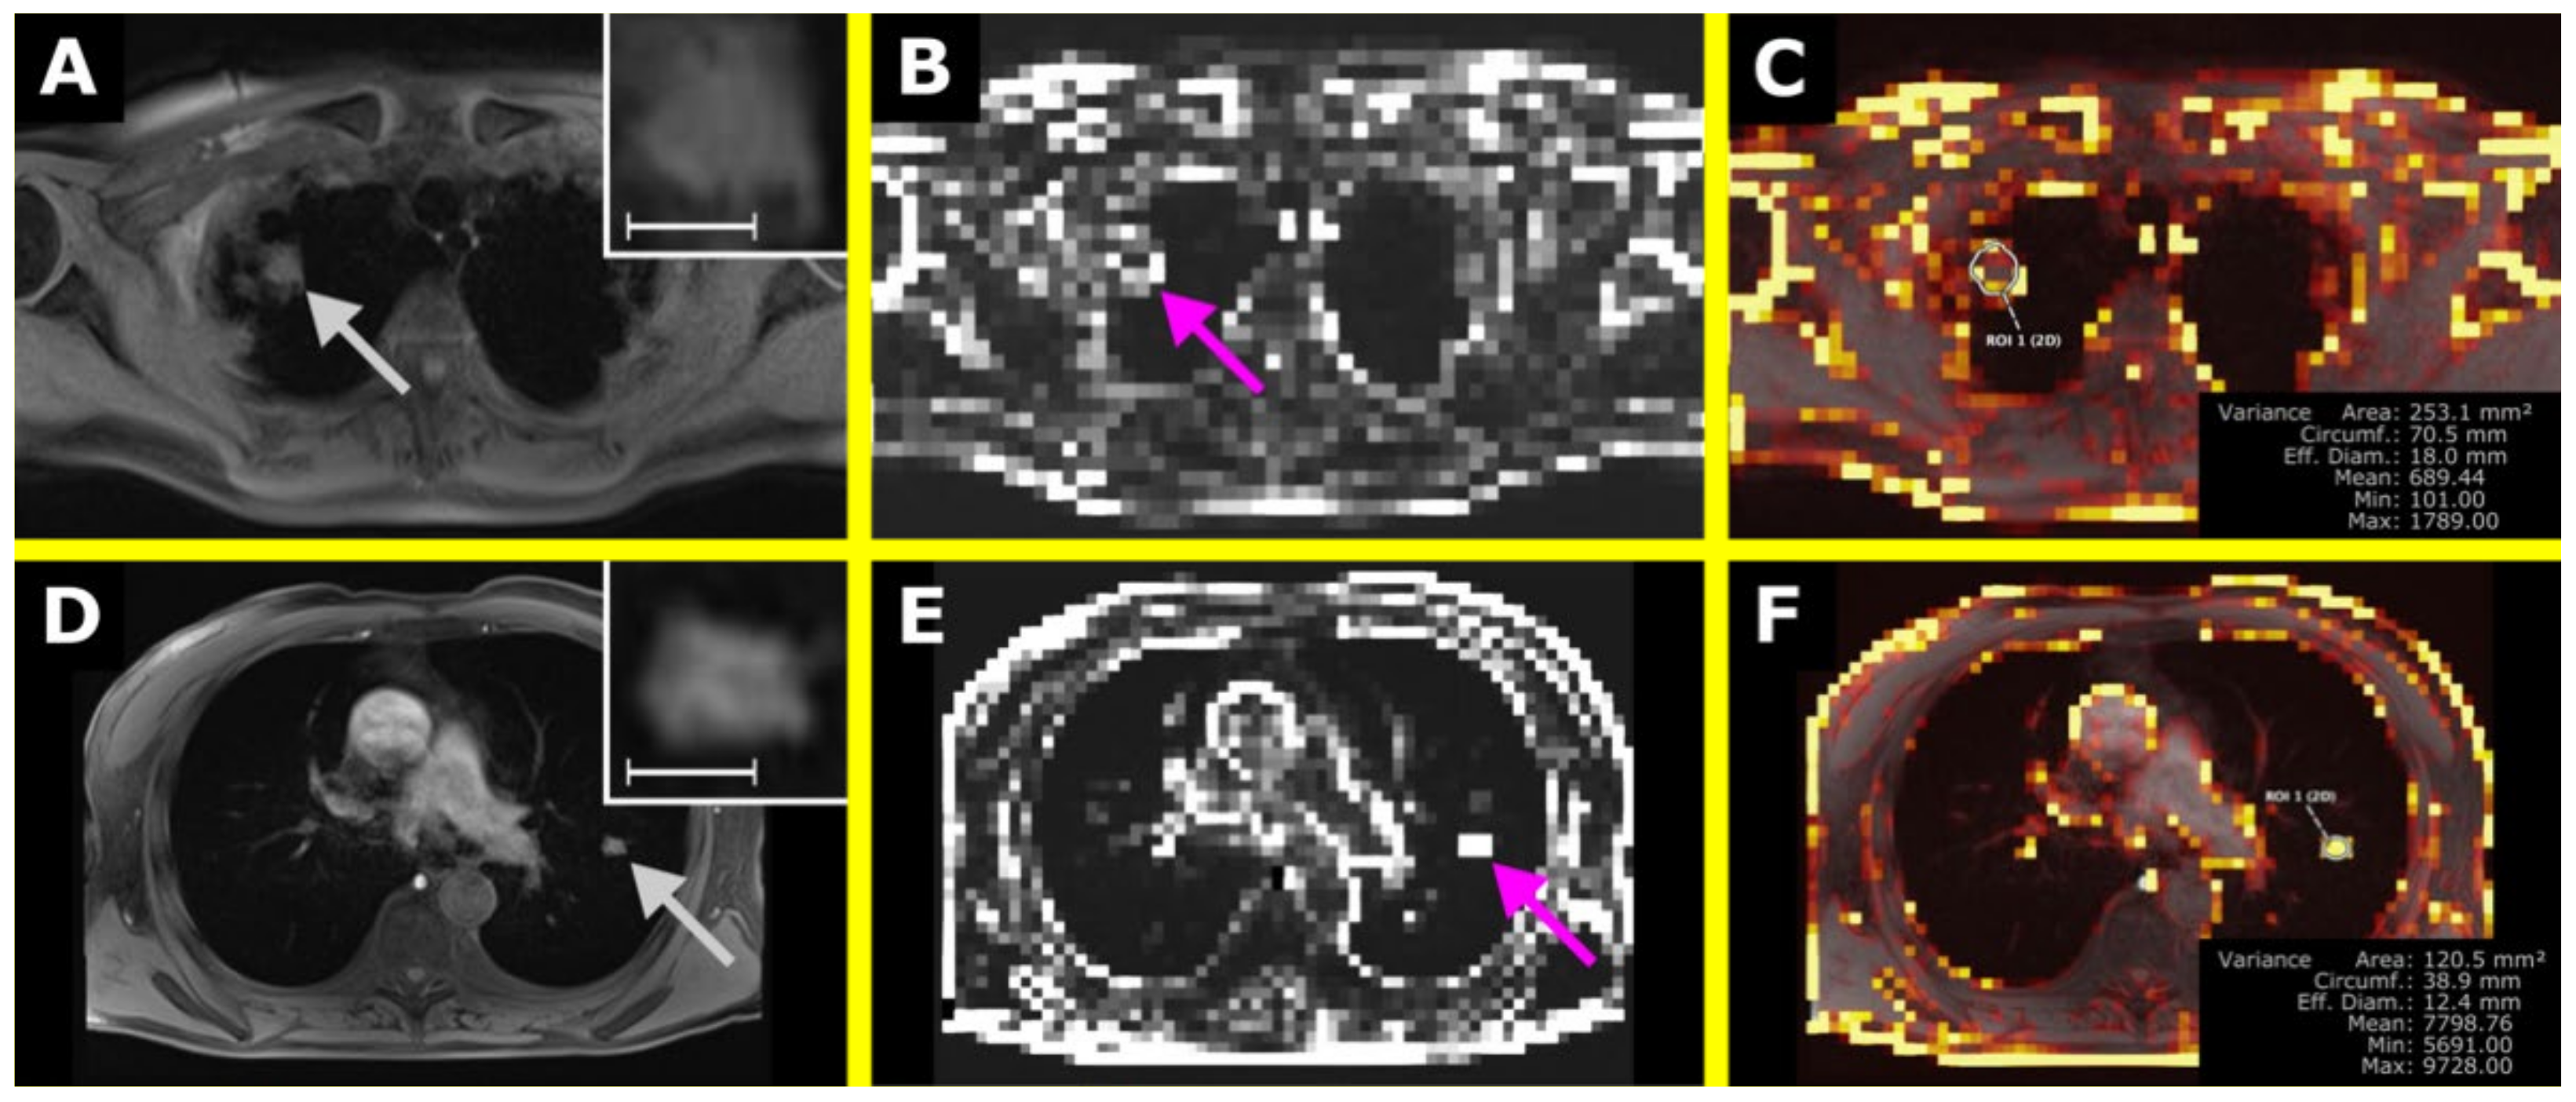

3.2. Clinical Application